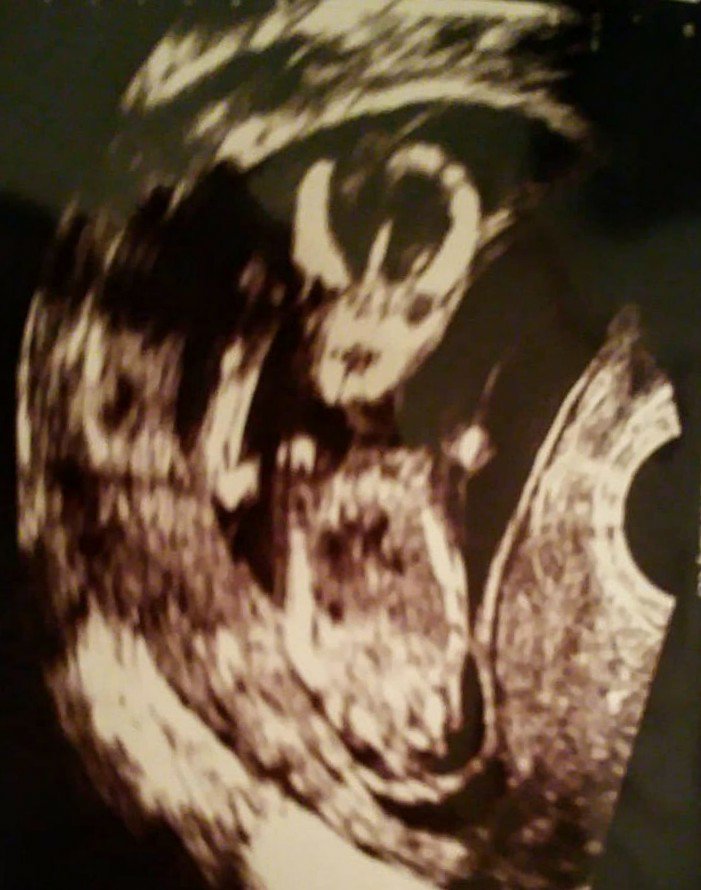

Chciałam tylko wrzucić fotki z ostatniego USG, miałam to zrobić w święta ale jakoś czasu brakło [emoji39]

Oto mój prawdopodobnie synek [emoji41][emoji7] zdjęcia z 21 grudnia [emoji6] na jednym z nich macha do was pozdrawiając [emoji6]Zobacz załącznik 928536Zobacz załącznik 928537